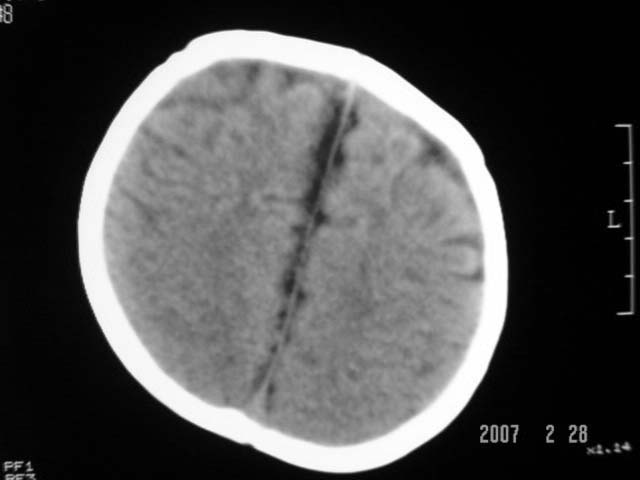

标题: PED0015:男,8M,发现不会坐立及神情异常,前囟已闭,双眼斜视, [打印本页]

标题: PED0015:男,8M,发现不会坐立及神情异常,前囟已闭,双眼斜视,

脑回较深,白质范围小,灰白质比例失调。余未见明显异常。

考虑:脑白质发育不良,必要时请做mri进一步检查。